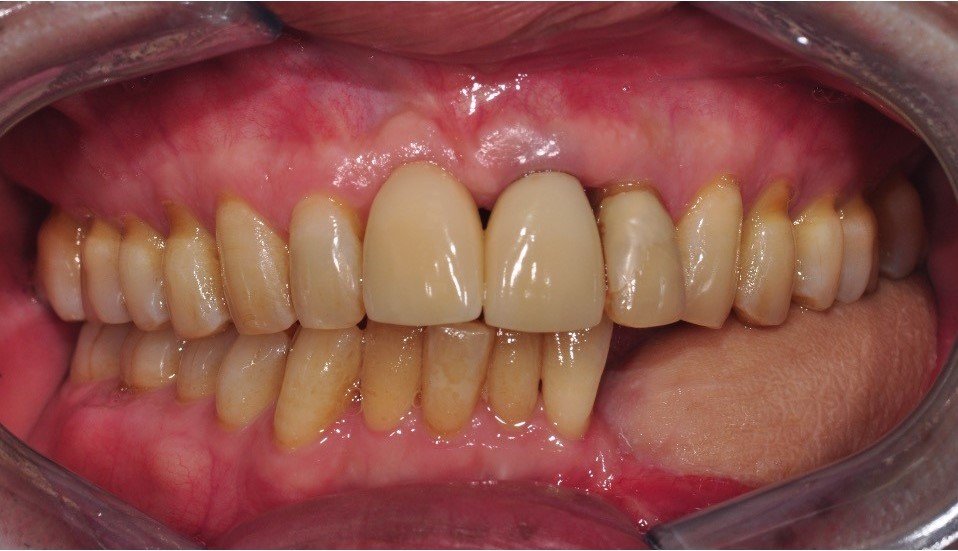

The removeable implant denture in place with a normal overbite and the decay removed and fillings placed.

-

The red carbon paper biting marks on the teeth illustrate a protective balanced hinge bite which is responsible for keeping the lower implant denture stable when chewing.

These abutments are easy to clean following removing the denture.

The final photograph of the implant denture supporting the lower lip and an improvement to the aesthetics of the upper teeth. The patient is currently treatment planned to completely replace the stained top left number 2 lateral incisor with a white bridge and other front teeth with aesthetic Zirconia/Porcelain crowns to colour match the whiter implant denture. The patient has returned twice yearly for a Continuous Care Appointment CCA for examination, fine tune bite adjustment and airbrush cleaning with chalk, air and water around the implant gumline followed by a fluoride application. The telescopic implant denture is now on its 10th year of longevity.